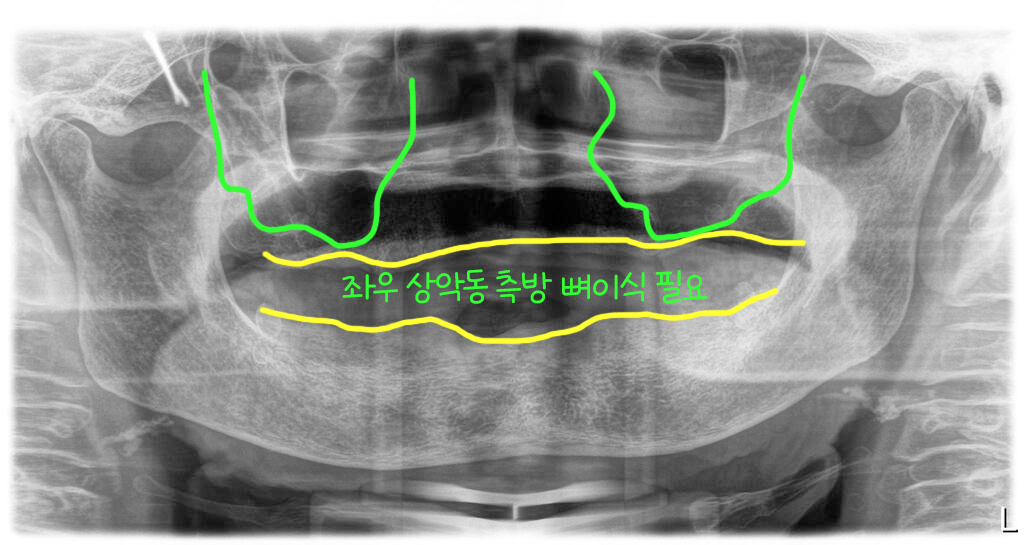

틀니를 하시려고 치아를 모두 뽑았고 잇몸은 모두 다 나은 상태로 내원하셨어요. 파노라마 엑스레이상으로 하악골은 양호한 편이었으나, 상악 구치부에는 상악동이 아래로 쳐져 있어 뼈가 부족한 상태였습니다.

그래서 전체임플란트로 치료를 결정하고 상악동 윈도우 방식의 뼈이식을 계획했어요.